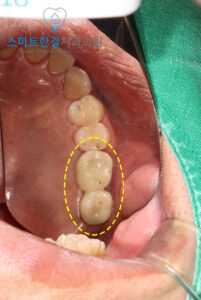

먼저 발치를 진행했어요.

임플란트를 식립하면서

뼈가 부족한 부위에

뼈이식을 진행했어요.

이를 통해 부족한 뼈를 보충하고,

임플란트가 안정적으로

식립될 수 있도록

기초를 마련했답니다.